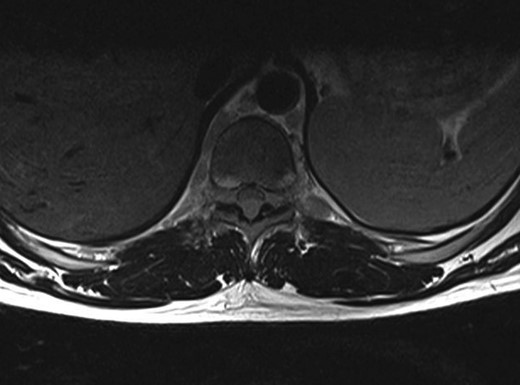

A 30-year-old male patient was admitted to our clinic with back pain. Pain was provoked by movements. The severity of pain was associated with the inability to perform the activities of daily living. The patient did not have any lymphoma-related B-type symptoms, including body weight loss, fever and sweat at night. He did not have a past and family history. There was no neurological deficit. Routine laboratory test results were normal. A magnetic resonance imaging (MRI) scan of the thoracic spine demonstrated an epidural tumor at the T9–11 level (Figs 1–3). The patient underwent spinal cord decompression via total laminectomy of T9–11 levels. Subtotal resection of the tumor was performed. Histological examination revealed the polymorphous cellular infiltration by histiocytes, large mononuclear cells and lacunar Reed–Sternberg cells with folded multi-lobed nuclei and small nucleoli (Fig. 4). Immunohistochemical staining was positive for CD15 and CD30 and negative for CD3, CD20, CD79a or CD45Ro. These features were most frequently observed in the mixed cellularity type of Hodgkin's lymphoma. Histological examination of the vertrebral body revealed no abnormality. The results of all other examinations (F-18 fluorodeoxyglucose positron emission tomography (F-18 FDG PET/CT), bone marrow biopsy and computed tomography (CT) of the chest, abdomen and pelvis) were negative for an occult disease. The patient was referred to the hematology department to undergo staged treatment. Six courses of chemotheraphy containing ABVD regimen (adriamycin, bleomycin, vinblastine and dacarbazine) were given to the patient. Postoperative MRI scan did not reveal any evidence of Hodgkin's disease (Fig. 5), F-18 FDG PET/CT, CT of the chest, abdomen and pelvis were obtained in 24 months and did not reveal any evidence of Hodgkin's disease.

Postoperative MRI scan did not reveal any evidence of Hodgkin's disease.

Moridaira et al. [4] reported a case of Hodgkin's disease at T8–10 epidural space. Rao et al. [6] published a case with primary spinal epidural Hodgkin's lymphoma. Our case is apparently the seventh case to be diagnosed with Hodgkin's disease who presented with spinal cord compression due to epidural space without lymphoma elsewhere. The abnormal MRI marrow signal of the T9 and T10 vertebral bodies can be seen in Fig. 5. Maybe the tumor in fact originated within the abnormal T9 or T10 bone marrow and spread to the epidural space via the epidural venous plexus. But histological examination of the vertebral body revealed no abnormality.